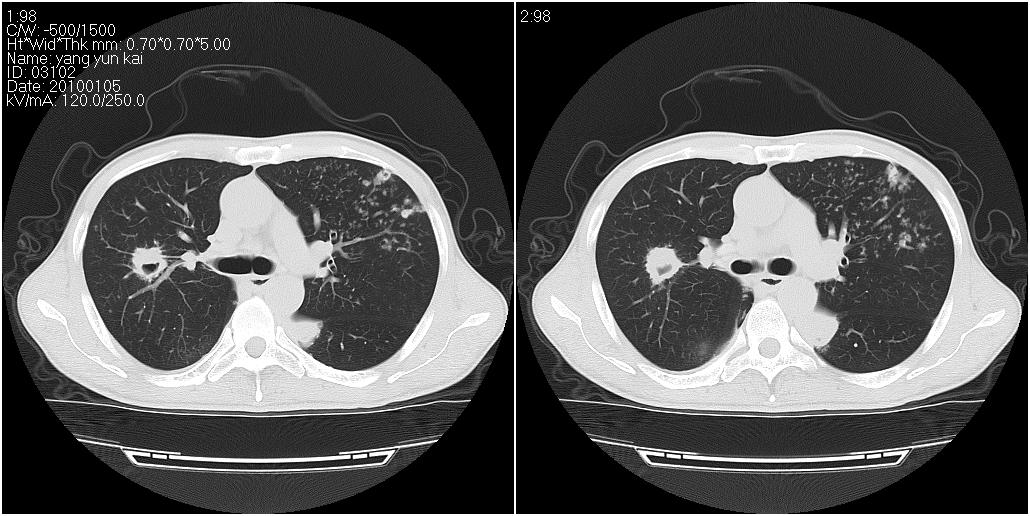

标题: CT23980:男性,47岁。近来咳痰、咳血,血沉增快(40左右),

男性,47岁。近来咳痰、咳血,血沉增快(40左右),痰中未检出结核杆菌。

两肺继发性肺结核并多发性结核球形成,部分病灶内空洞形成。

符合继发性结核表现部分空洞形成并播散